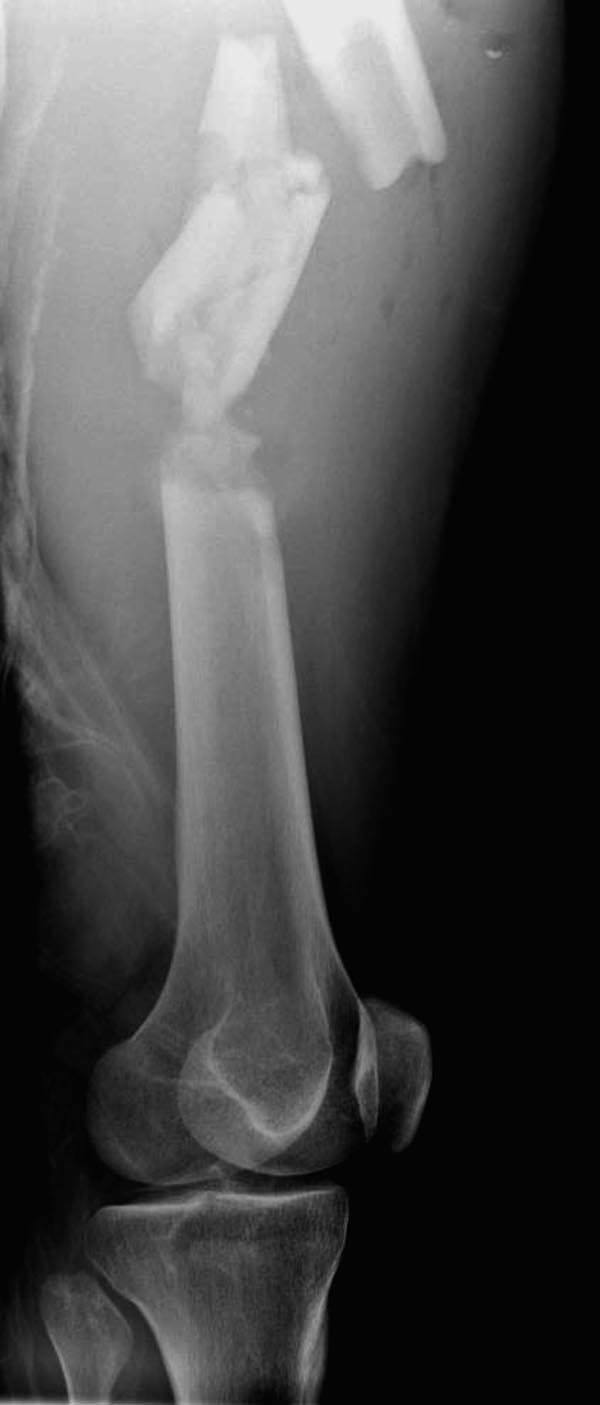

В фиксации тибиал плато надо соблюдать осторожность, потому что по снимку кажется поврежденной только медиальная часть, и медиальные переломы имеют тенденцию вовлечения задней поверхности плато. Боковой снимок покажет, куда идет линия перелома, а также покажет состояние перелома надколенника. Фиксировать надо buttress-опорной пластиной иначе винты не удержат варусный коллапс. В зависимости от вовлечения разгибательного механизма фиксация надколенника.

Здесь выставлен ренгенограммы больного, ему 21, травму получил в результате высокоскоростной погони на украденной машине, которая закончилась смертью трех остальных “боевых комрадов”. Начатую коллегой открытую операцию на шейке пришлось закончить мне, установкой винтов и ретроградной фиксацией бедра. Выписка в обычное сроки и наблюдался амбулаторно. Каждый раз напоминали о возможности осложнений ввиде несращения! По истечению 4 месяцев появились признаки варусной деформации. На СТ срезах несращение шейки и бедра. Риминг, замена на более толстый гвоздь и вальгусная остеотомия.